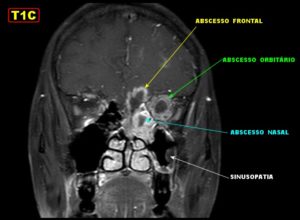

Если воспалительный процесс не проходит из-за отсутствия или неправильного лечения, то инфекция мигрирует в рядом расположенные отделы. Впоследствии из-за этого может возникнуть менингит, энцефалит (скопление гноя в мозговых оболочках), абсцессы и тромбоз сосудов головного мозга. Другие осложнения включают ухудшение зрения, вплоть до необратимой слепоты.

Осложнения

Осложнения сфеноидита определяются соседством клиновидной пазухи с важными образованиями, которые могут вторично вовлекаться в воспалительный процесс. Рядом располагаются:

- Сонные артерии и вены;

- Гипофиз – важная эндокринная железа и нервный центр регуляции многих процессов;

- Глазничные нервы;

- Участки головного мозга, расположенные в области основания черепа.